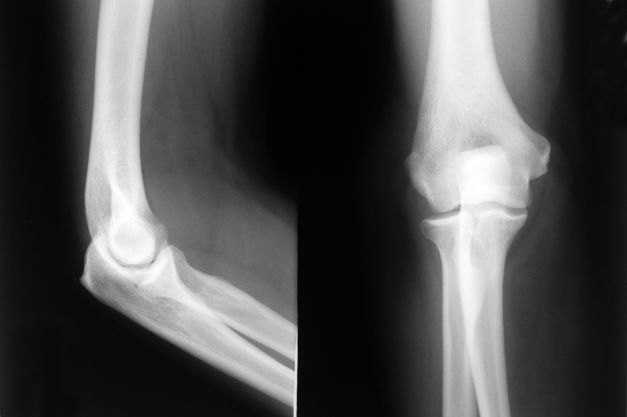

YPER 13/03 - In het Jan Yperman Ziekenhuis in Ieper is vrijdag een halve elleboogprothese geplaatst bij een patiënt. Het gaat om een ingreep die wordt toegepast bij patiënten met artrose aan de buitenzijde van de elleboog. In België is het Jan Yperman Ziekenhuis voorlopig het enige ziekenhuis dat deze ingreep aanbiedt.

Artrose van de elleboog komt minder vaak voor dan artrose van de heup of knie, maar het veroorzaakt veel pijn. Een oplossing is het plaatsen van een prothese. Zo werd in het Jan Yperman Ziekenhuis vrijdag een 'halve elleboogprothese geplaatst. "Daarbij wordt enkel het beschadigde deel van de elleboog vervangen, het scharniergewricht zelf blijft intact. Daardoor revalideert de patiënt in principe veel sneller", klinkt het.